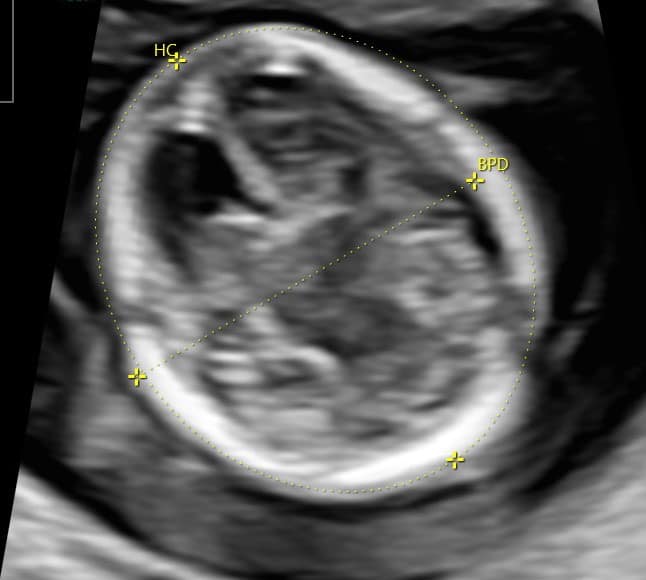

Agykoponya: Már megjelenik a kisagy, az agykamrák és az agyban található üregek, agytörzs mellett már vizsgálható a kérgestest, mely a két féltekét köti össze. Megjelenik az agy első barázdája is, egyebekben még az agy sima felszínű, nem barázdált, mint később.

Magzati koponya, arc: koponyacsontok, agykamrák a bennük látható érfonatokkal, a hátsó koponyagödör fejlődő területei, agytörzs.